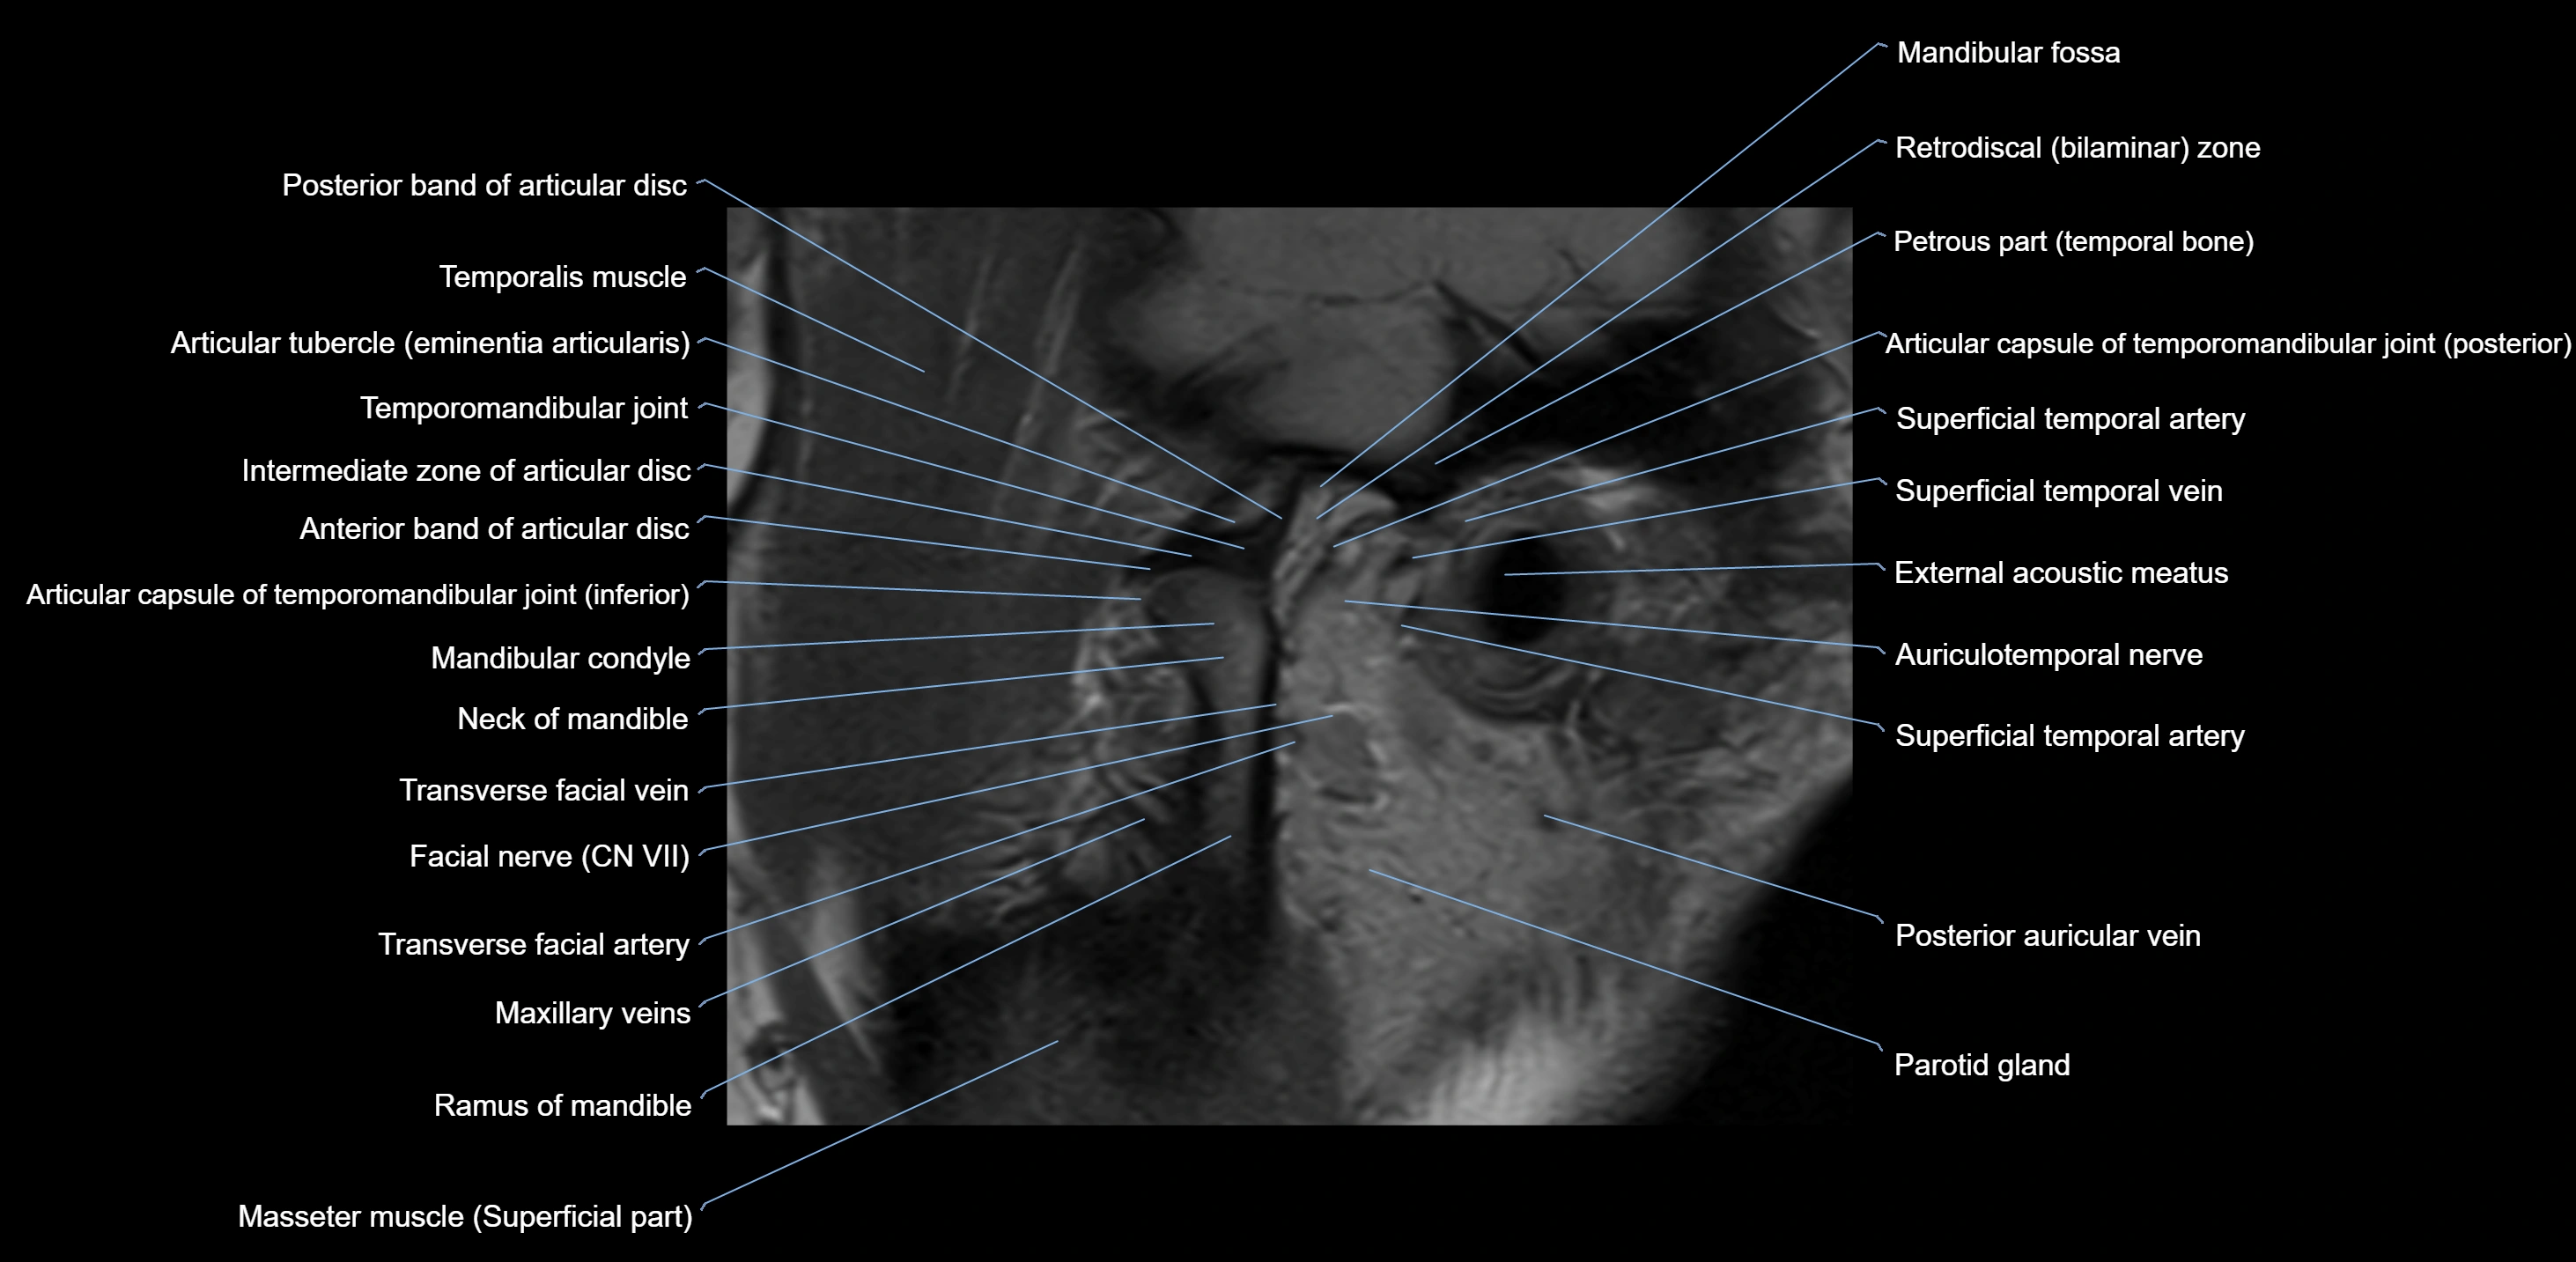

MRI appearance

T1-weighted images:

• Cortical bone: Low signal intensity

• Cancellous marrow: Intermediate to high signal depending on fatty content

• Teeth: Signal void structures

• Adjacent soft tissues: Normal gingiva and oral mucosa signal

T2-weighted images:

• Cortical bone and teeth: Low signal

• Marrow: Intermediate signal